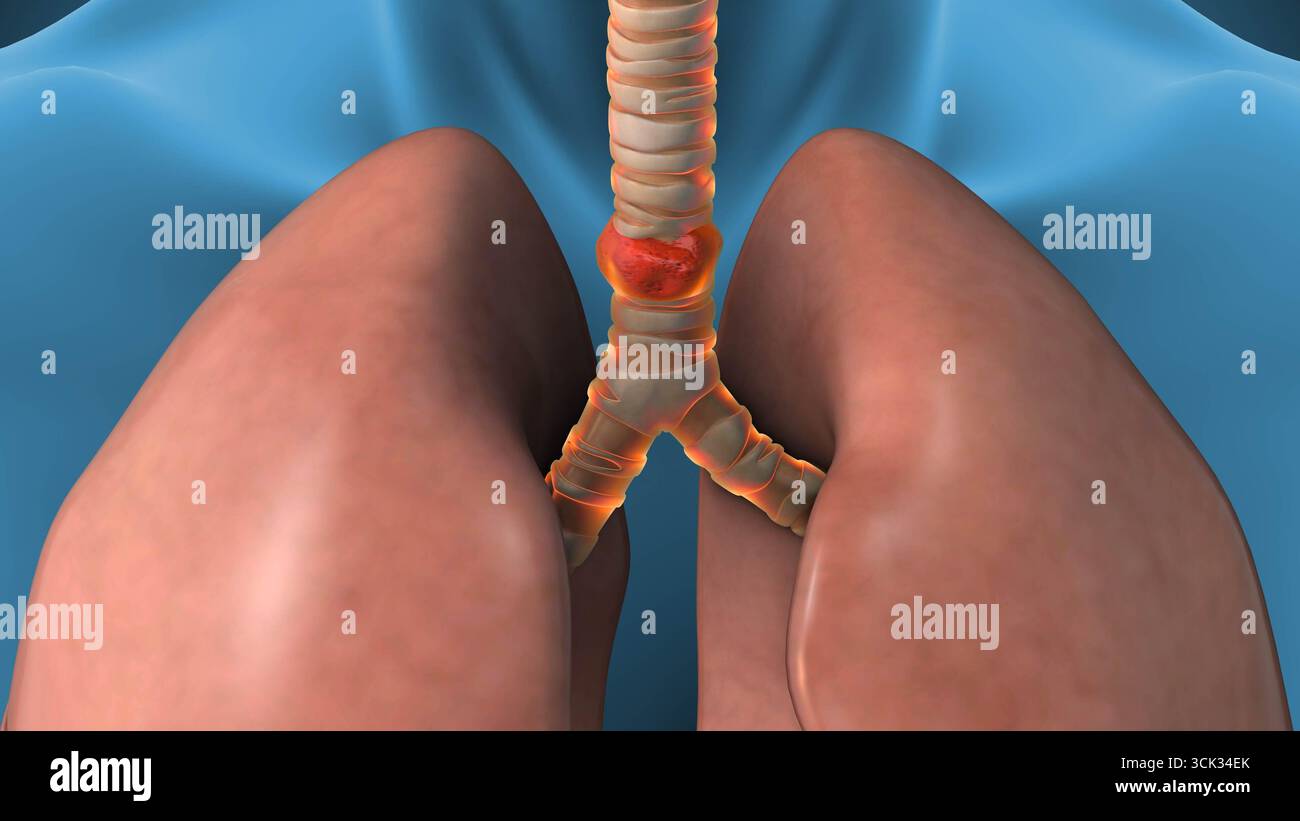

RF2A86M1N–La pneumonie et alvéoles pulmonaires de liquide ou de l'anatomie de l'inflammation alvéolaire du schéma d'un concept médical anatomie pulmonaire et respiratoire.

RF2A895XN–La pneumonie et alvéoles pulmonaires avec schéma fluide ou inflammation alvéolaire schéma anatomique comme un concept médical des poumons sains et malsains.

RF2WJ0PA6–Pneumonie. Etat inflammatoire des poumons. La section transversale de l'alvéole normale et les alvéoles sont remplies de liquides. Affiche vectorielle. Plat isométrique